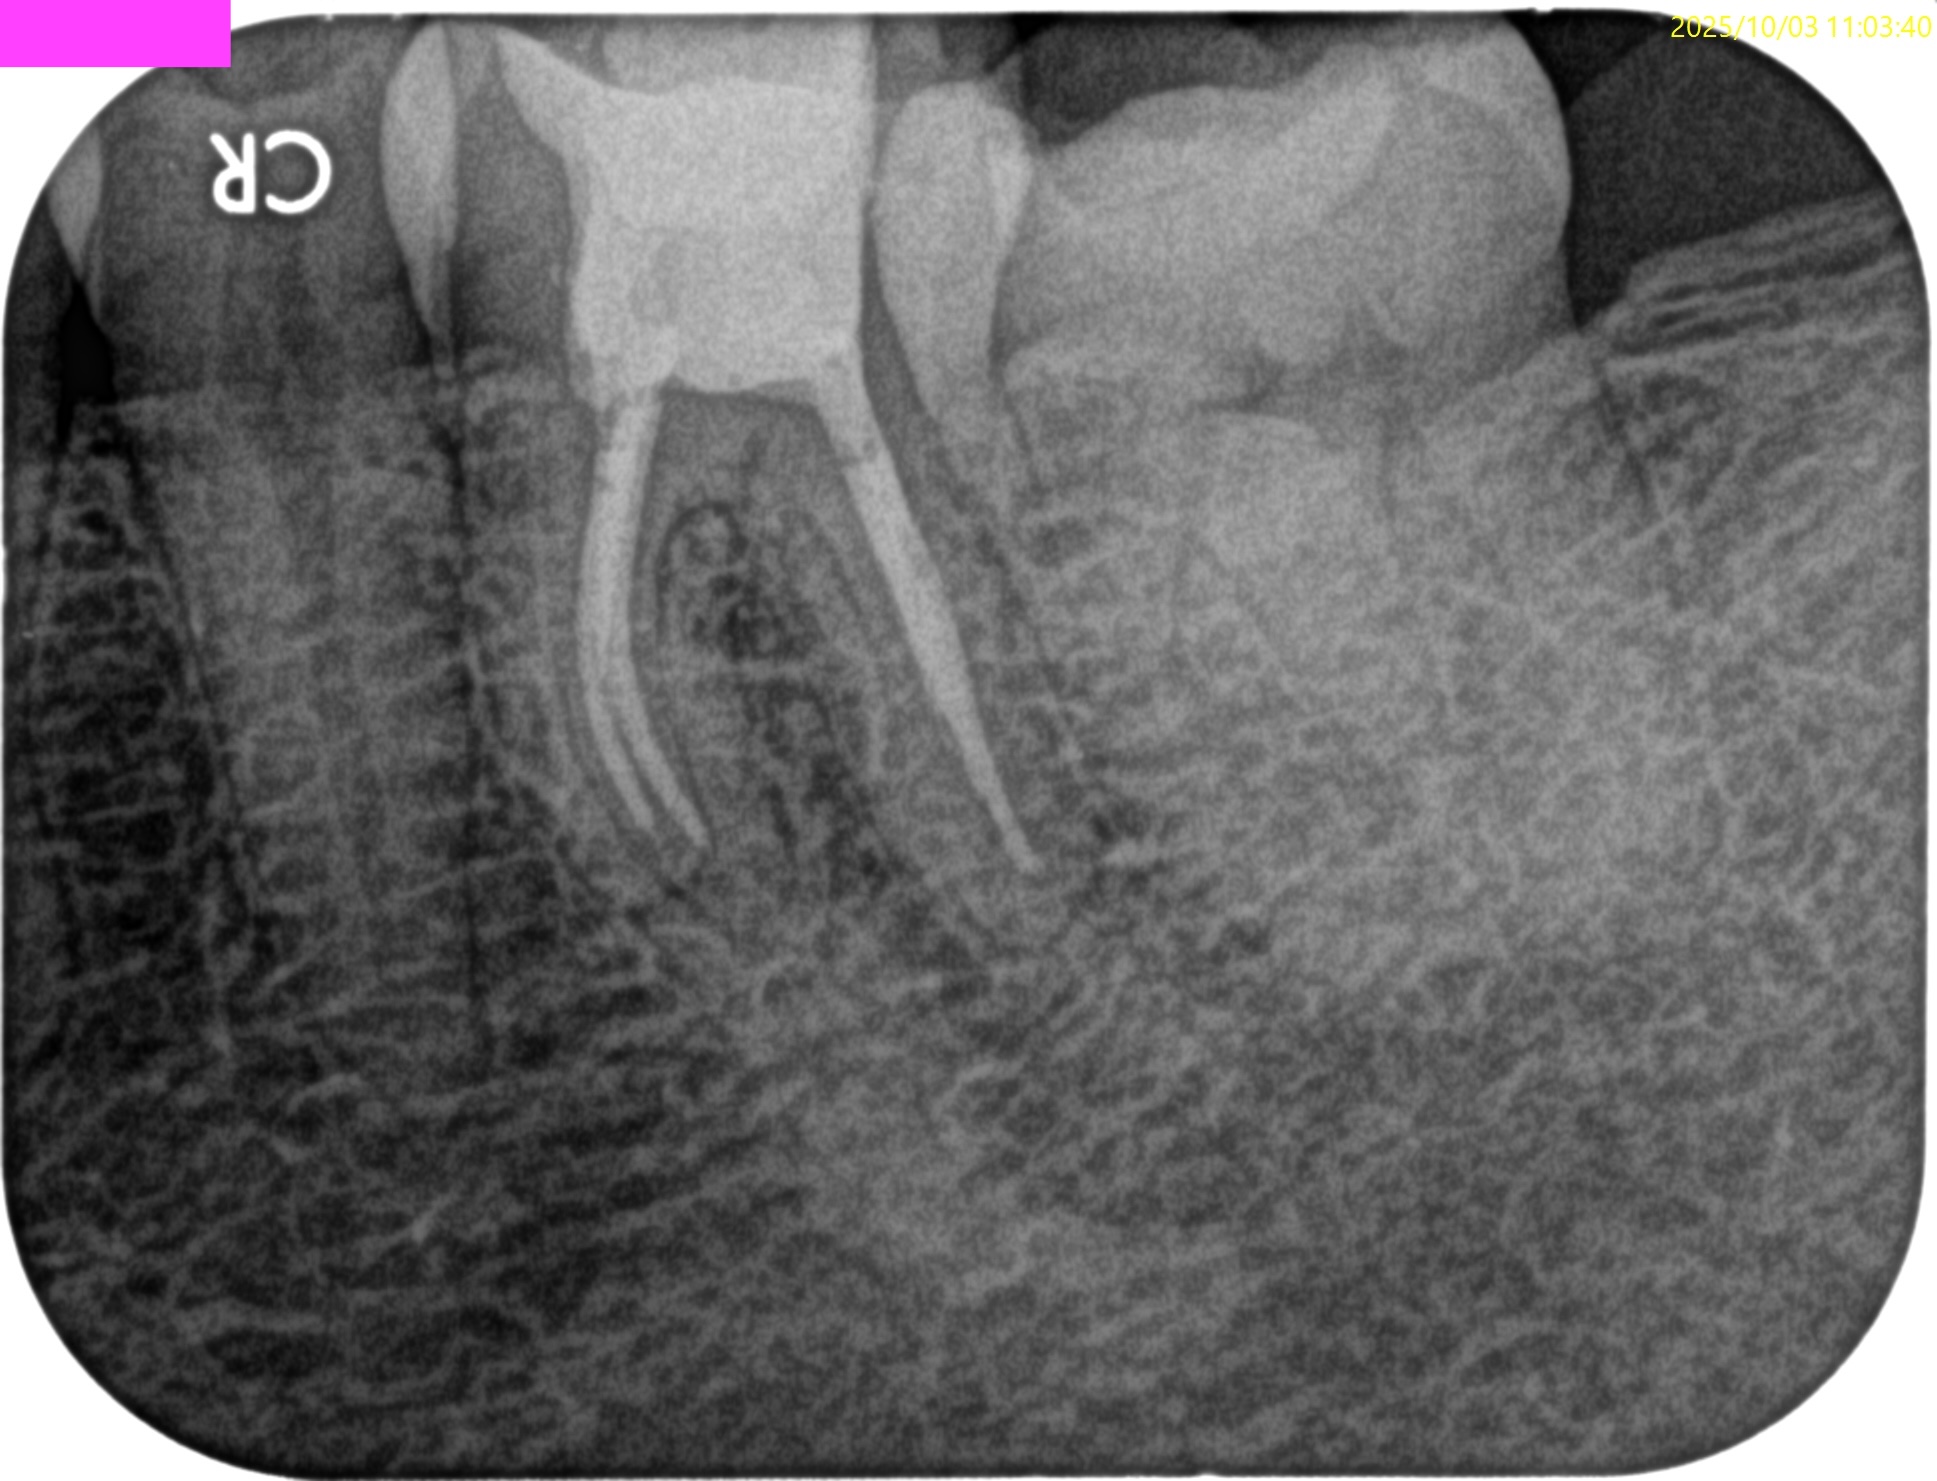

チャンバーオープンした。

やはり血まみれだ。

以下のように根管形成した。